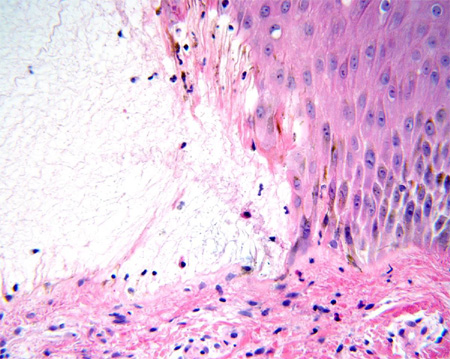

Penfigoide bolhoso

Microscopia óptica: vesícula subepidérmica

Do acervo da Dra. Vesna Petronic-Rosic